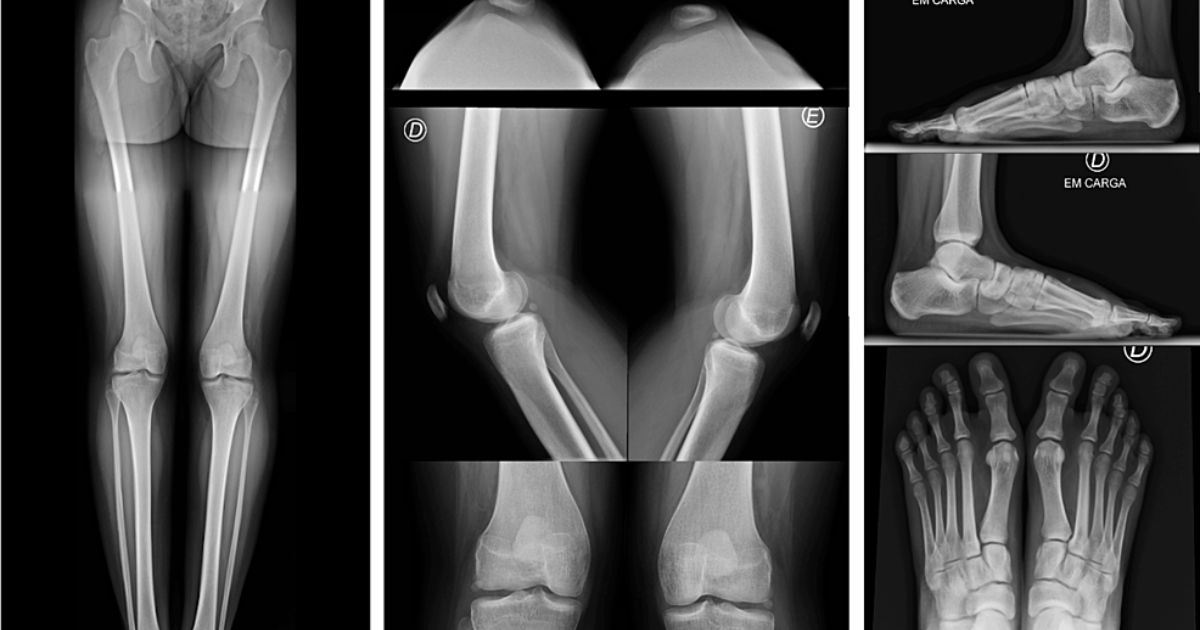

Thiểu sản xương cũng là một trong số các dấu hiệu của bệnh

Triệu chứng ở xương chậu

Khoảng 30–70% người bệnh có xương chậu bất thường, thường được mô tả là có “sừng chậu” (iliac horns). Đây là những mấu xương nhỏ nhô ra ở mặt sau xương chậu, có thể nhìn thấy qua ảnh X-quang. Mặc dù không gây đau hay ảnh hưởng lớn đến sức khỏe, sừng chậu là dấu hiệu đặc trưng giúp bác sĩ nhận biết NPS trong chẩn đoán hình ảnh.

Khi nghi ngờ NPS, bác sĩ có thể chỉ định chụp X-quang xương chậu và khớp khuỷu để tìm hình ảnh đặc trưng như sừng chậu hoặc biến dạng xương bánh chè.